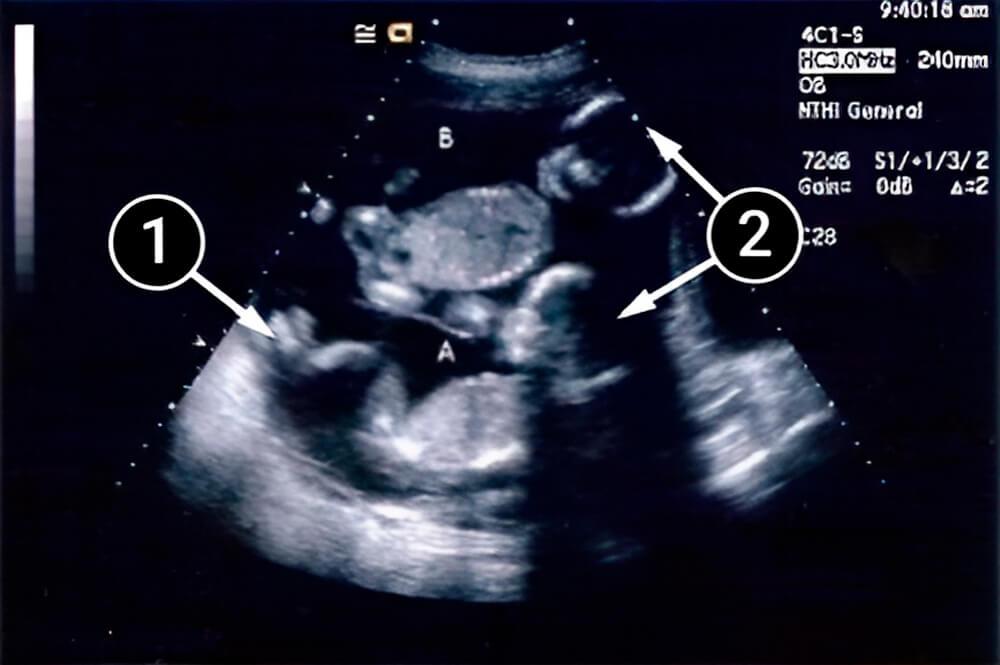

La imagen muestra al bebé al final de la semana 19 de desarrollo. Se acuesta sobre su lado izquierdo, frente a la pantalla.

Un contorno claramente definido de la cabeza permite diferenciar, a detalle, los huesos frontales, los huesos nasales emparejados y la barbilla o mentón. Las mandíbulas superior e inferior están separadas por una franja estrecha: se trata de la boca.

la placenta

manos

cabeza